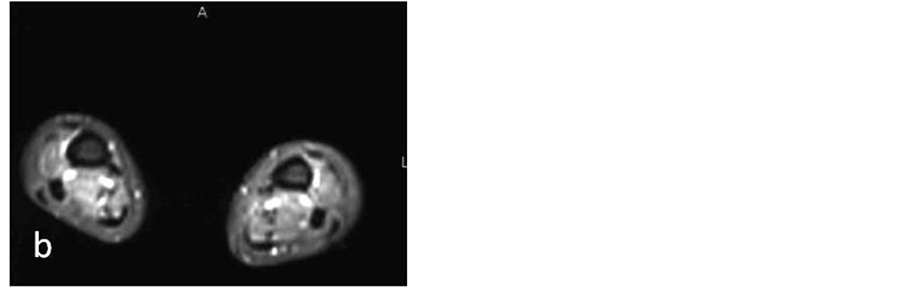

The last patient underwent both lower extremities MRI which showed myositis of the tibial muscles bilateral (Figure 3). Although this pt did not reveal any neurological symptoms, because of the presence of APS, she underwent brain MRI to detect possible cerebrovascular involvement. The brain MRI was abnormal with subcortical lesions extended to the cortex in the left parietal lobe, focal lesions in the deep white matter bilateral, as well as porencephalic lesions with peripheral gliosis on the left parietal lobe, compatible with old infarct. No pathologic enhancement was noticed (Figure 4).

Figure 3. (a) Sagital, (b) axial MR Fat-Saturation images show (a) diffuse hyperintensity within the tibial muscles (arrow) with mild post contrast enhancement (b), findings consisted with myositis.